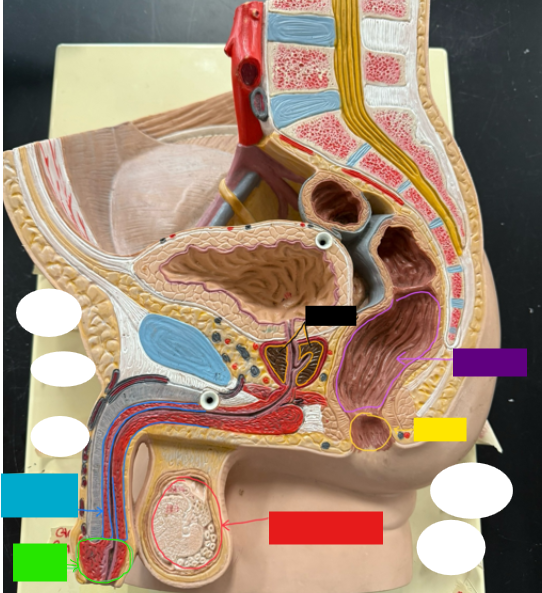

What is the name of the blue box?

Corpus spongiosum

What is the name of the light green box?

Glans penis

What is the name of the red box?

Seminiferous tubules

What is the name of the black box? X2

Prostate

What is the name of the purple box?

Rectum

What is the name of the yellow box?

Anus

What is the name of the red box?

Scrotum

What is the name of the orange box?

Corpus cavernosum

What is the name of the light blue box?

Spongy urethra

What is the name of the red box?

Prostatic urethra

What is the name of the pink box?

Ejaculatory duct

What is the name of the yellow box?

Membranous urethra

What is the name of the brown box?

Testis